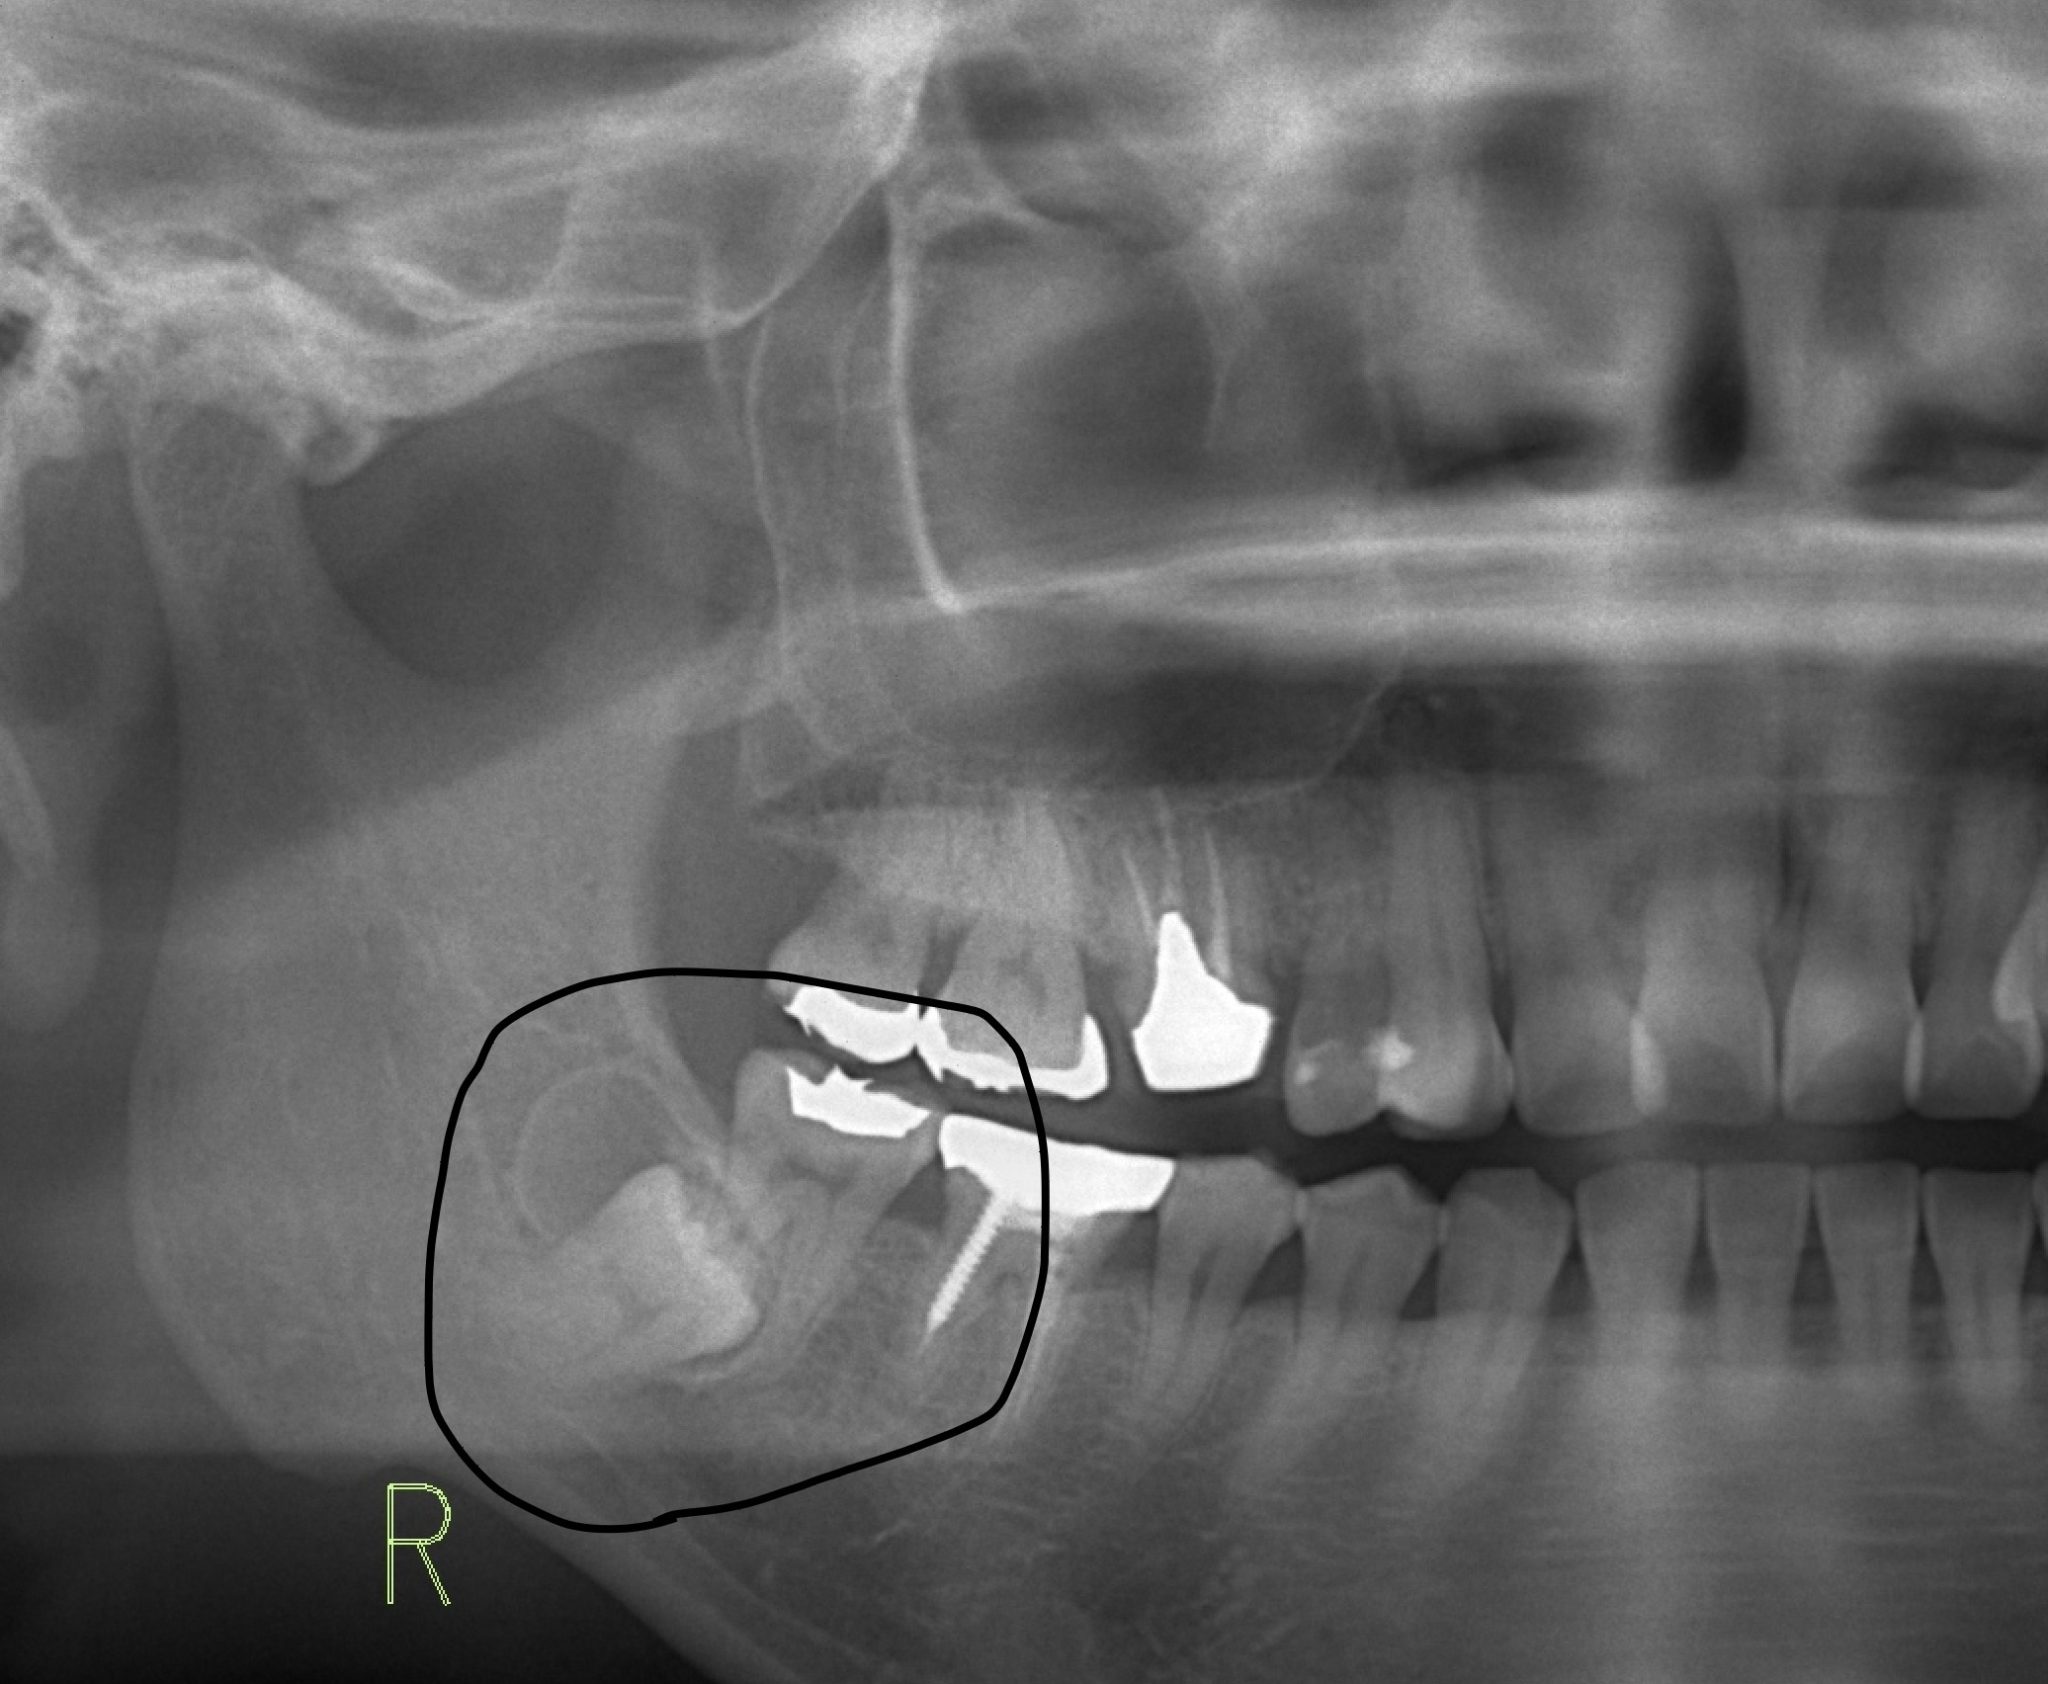

場合によっては、定期的な健康診断で医師が濾胞性嚢胞があることを知ることがあります。あなたが出産可能な年齢で、それ以外は健康で、何の症状も示さない場合、医師は嚢胞が自然に解決するまで放置する可能性があります。定期検査の際にそれが成長していないことを確認するために監視する場合があります。場合によっては、膣超音波検査やその他の検査も推奨される場合があります。

下腹部の痛みやその他の症状がある場合、医師は原因を診断するために内診を行うことがあります。症状や病歴に応じて、超音波検査、CT スキャン、MRI スキャン、その他の検査も推奨される場合があります。医師が正確な診断を下すことが重要です。破裂した嚢胞の症状は、多くの場合、虫垂炎や他のいくつかの病気の症状と似ています。